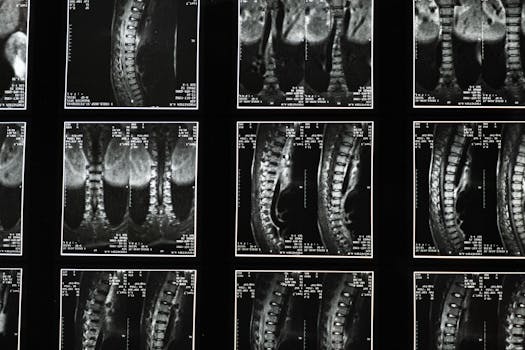

The term “limbus vertebra” may not be familiar to many, but understanding it can be important for assessing spinal health. A limbus vertebra typically occurs… Continue Reading